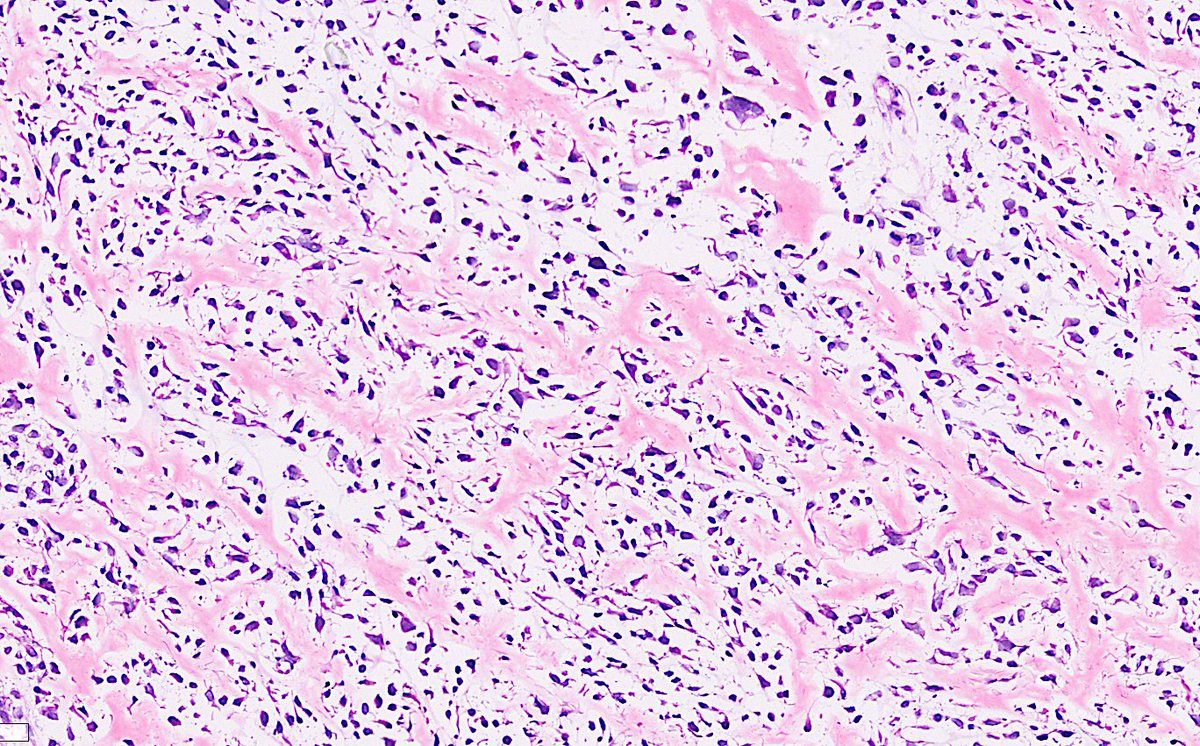

Middle-aged patient with a mass in a cervical vertebra. There is a hx of sarcoma. This was not my own case, but I was fortunate enough to see it and learn from it, hence the reason I'm sharing. Morphology is 🔑 #IHCPath provided is PCK. What's your diagnosis? #PathTwitter